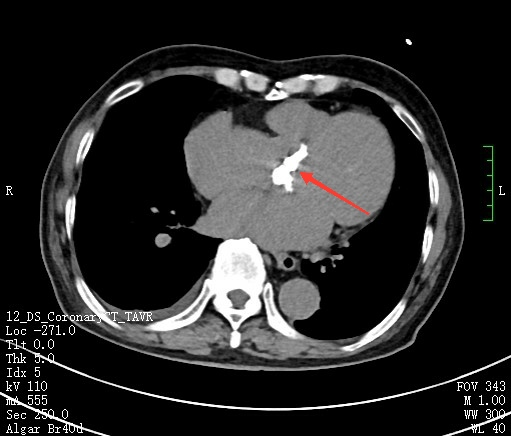

杨嗲嗲既往有“肺气肿”、“颈动脉粥样硬化”、 “胆囊结石”、 “前列腺增生”等病史。心脏彩超显示主动脉瓣钙化、重度狭窄并返流,冠脉影像显示冠状动脉病变也很严重。

冠脉造影,红色箭头提示冠脉左回旋支严重狭窄